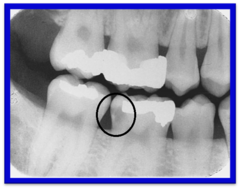

root absess

Front

collection of puss at apex of root. appears as radiolucent circle

Back